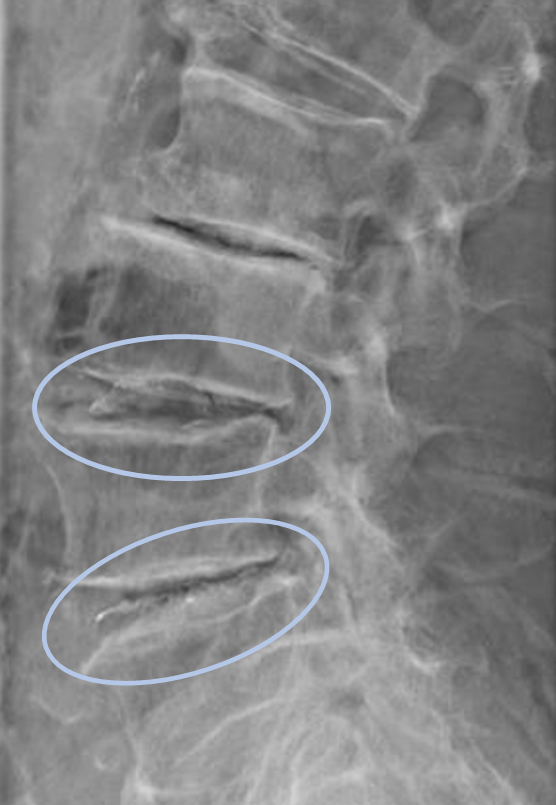

患者様と相談の元、L3/4,4/5にセルゲル法を施行

DiscoGelを入れた後の画像になります。